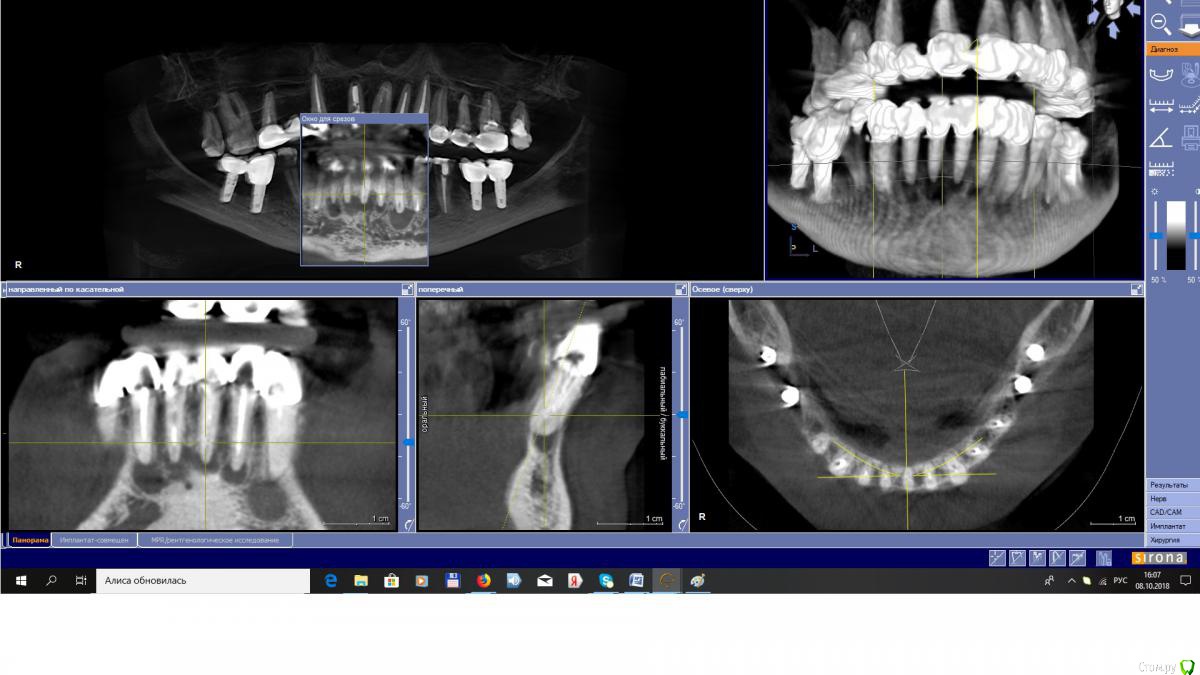

EEcho Опубликовано 10 октября, 2018 Поделиться Опубликовано 10 октября, 2018 Добрый день, Коллеги!Какие варианты в данной ситуации? Удалять, одномоментно импланты и временный протез, или удалять, ждать, НКР, импланты, временный протез. Или, еще какие решения? Ссылка на комментарий

EEcho Опубликовано 10 октября, 2018 Автор Поделиться Опубликовано 10 октября, 2018 повторное эндо Судя по снимку, на корнях уже сформированные кисты со сформированной оболочкой, Какая вероятность, что при таких условиях, кисты регрессируют? На форумах и в журналах положительную динамику встречал, но на практике - очень редко. 2 Ссылка на комментарий

Дмитрий Л. Опубликовано 10 октября, 2018 Поделиться Опубликовано 10 октября, 2018 Там вопрос больше в пародонтите, если пародонтальный карман имеет связь с "кистой", вероятность добиться успеха минимальна, но по этим срезам трудно сказать.Я поддерживаю эндо.Имплантация в этом участке имеет самый низкий процент успешности, к тому же вертикальной высоты может не хватить, и вестибюлярной стенки наверняка нету. Зубы с одним прямым каналом, распломбировать нетрудно будет. На кальцие провести. Контроль раз в 2 месяца прицельными снимками. Ссылка на комментарий